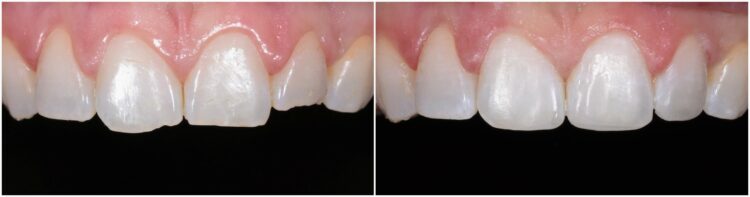

Estetické sanace

Přímé fasety z kompozitních materiálů, korekce tvaru zubů, cervikální defekty, plošné kazy po ortodontické léčbě.